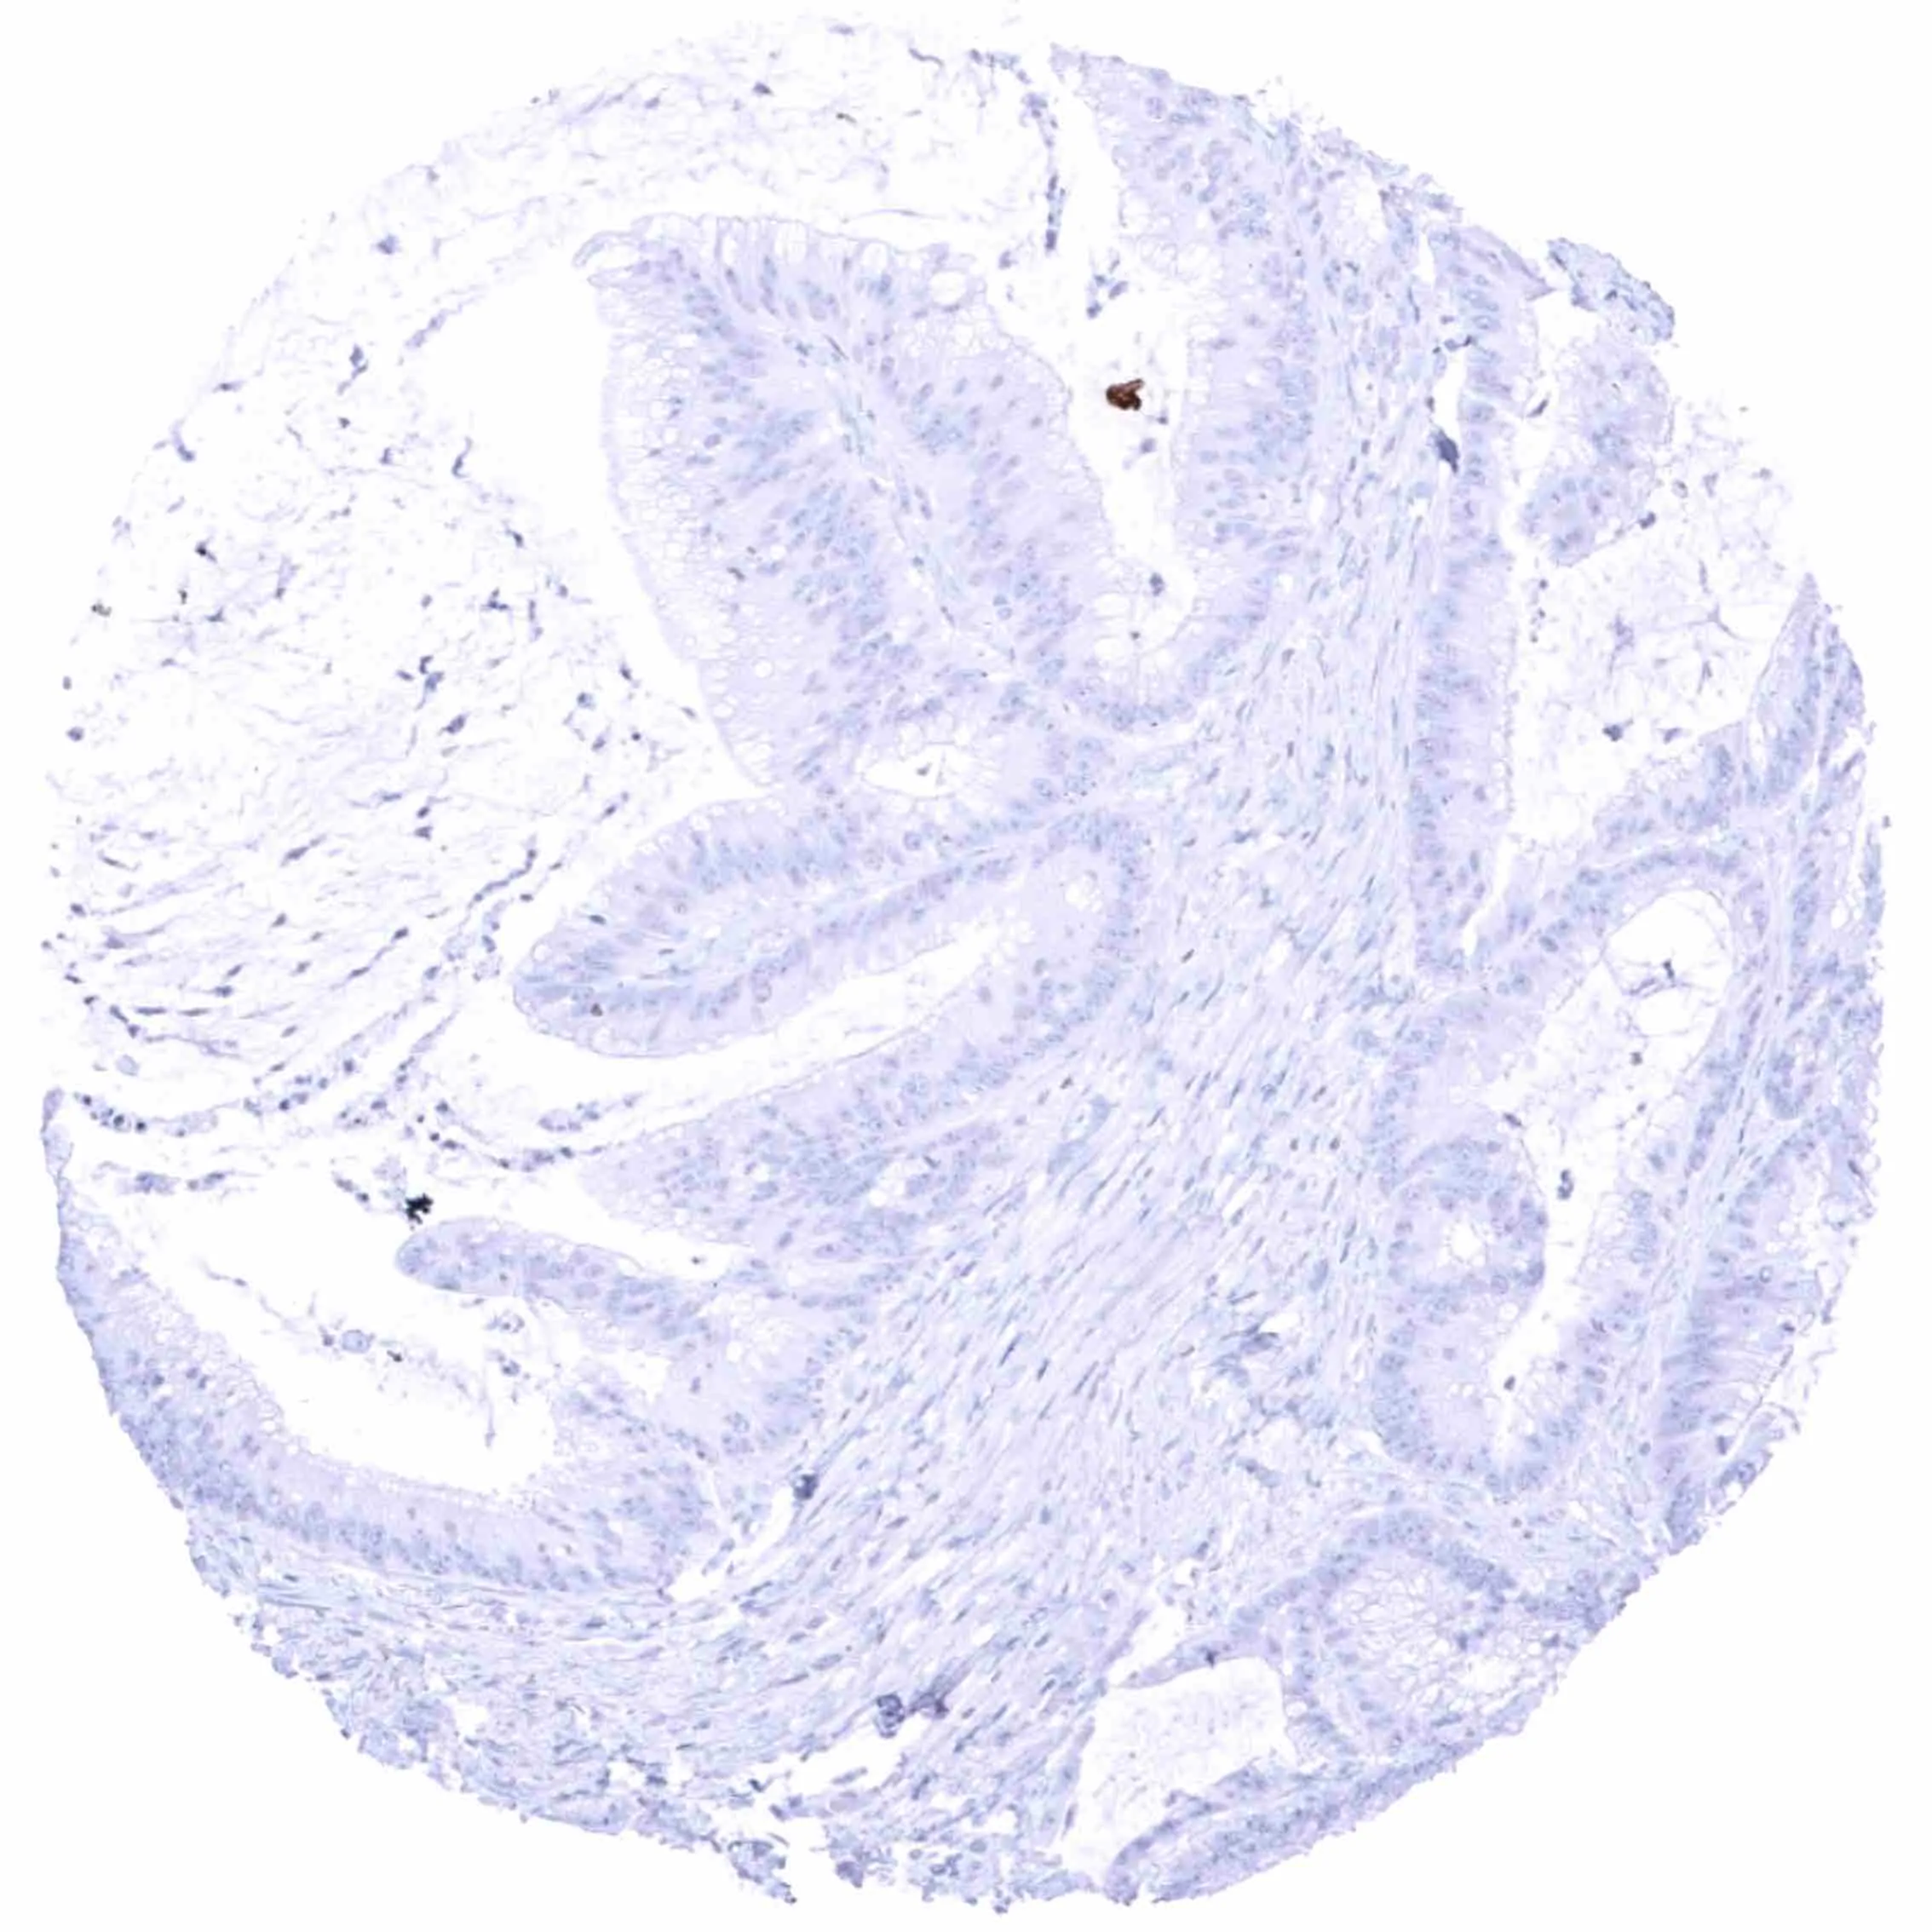

Colon – EGFRvIII negative colorectal adenocarcinoma.